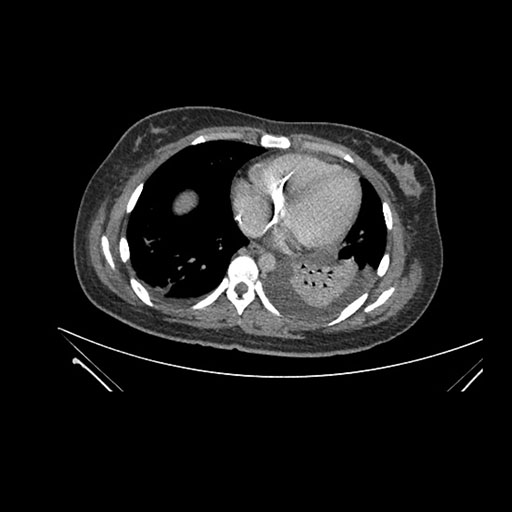

Imaging Analysis

Look through the patient's CT scan to identify any areas of concern for the necessary procedure.

Axial Arterial